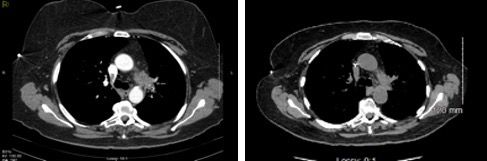

Six months following her surgery, a routine annual screening mammogram revealed 2 new adjacent nodules in the lower central right breast suspicious for breast cancer (Figure 3). Ultrasound guided biopsy of these lesions revealed adenocarcinoma consistent with metastasis from lung primary (Figure 4). A restaging PET-CT scan revealed new hypermetabolic lesions involving caudate lobe of liver, left adrenal gland, and bone lesions in left humerus, right scapula, and right ischium, which were totally asymptomatic (Figure 5).

Figure 3. Right mediolateral oblique digital mammogram view shows 2 adjacent nodules in the lower breast. Margins are slightly lobulated. The finding was new from the prior mammogram and suspicious for malignancy.